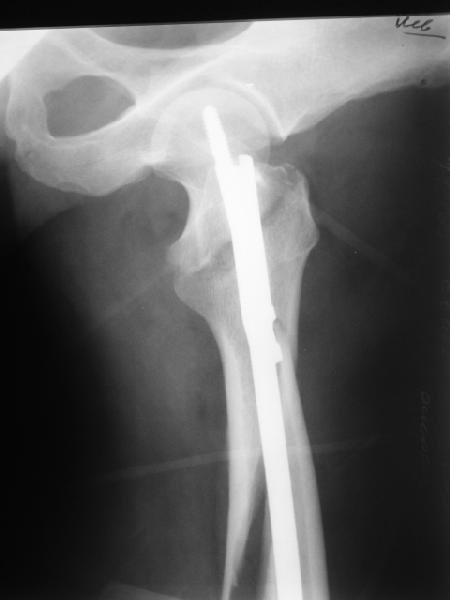

Дорогие коллеги,Как правильно определить такой перелом по классификации AO?

Как два отдельных или есть один соответствующий код? Фиксировать-то оба можно одним фиксатором...

Как раз недавно у меня был примерный случай: больному 36 лет, поступил ночью, травма в результате мотоциклетной аварии, кроме чрезвертельного и спирального перелома левого бедра имеется переломы костей предплечья с этой же стороны. Скелетное вытяжение, а на следующий день больной про оперирован на ортопедическом столе с дистракцией. Чтобы не расколоть чрезвертельный перелом провели временную спицу ближе к переднему кортексу, из малого разреза костодержатель для репозиции, а фиксацию провели антиградным штифтом. Этапы операции на снимках.

Да, сейчас это и у нас самый напрашивающийся выбор. Сделали гвоздем ChM, картинки в приложении.